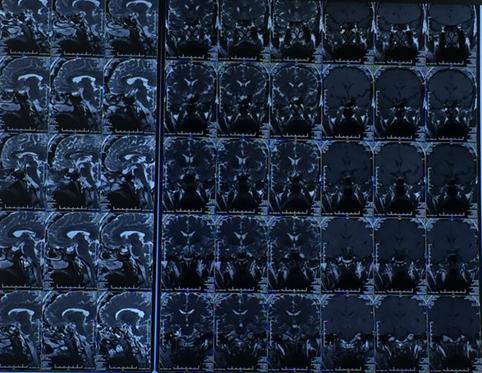

术前影像学检查:

诊断:生长激素型垂体瘤